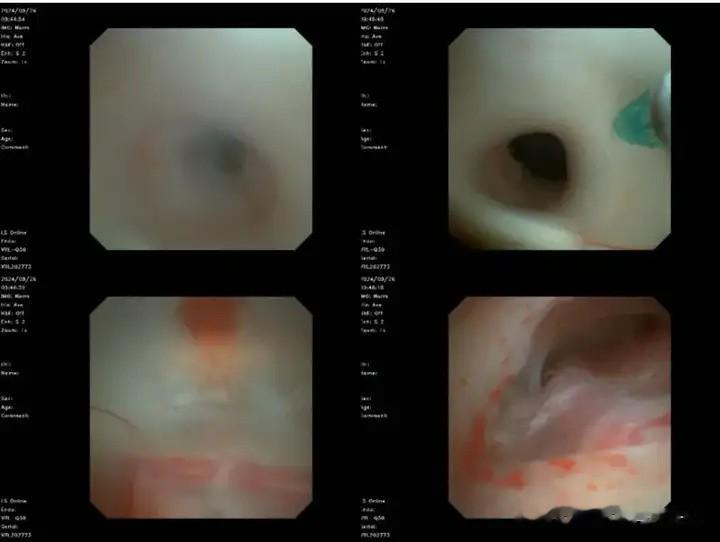

手术室内,气氛紧张而庄重。肖庆主任亲自操刀,软性神经内镜如同一条灵动的蛇,通过原先的手术骨孔,缓缓进入患儿的脑室系统。随着内镜的深入,一幅幅清晰的脑室图像呈现在屏幕上。凭借扎实的解剖功底,肖庆主任发现患儿的脑室系统内存在着严重的粘连和感染迹象。他果断地决定尽可能为小玥还原结构复位,神经内镜探查术 + 导水管成型术 + 显微镜下第三脑室底造瘘术 + 脑脊液置换术 + 原分流管去除术 + 脑室外引流术。这一连串的手术操作,犹如一场精心编排的舞蹈,每一个动作都精准无误,每一个步骤都至关重要。

软性内镜观:可见导水管处膜性梗阻及基底动脉周围粘连